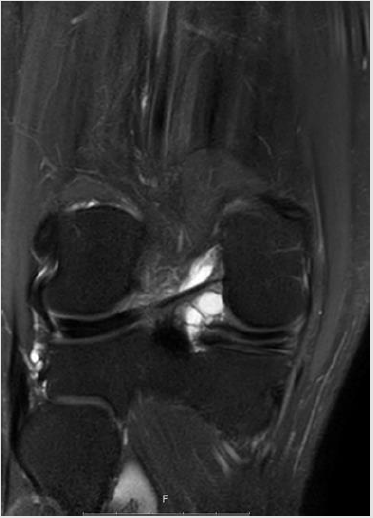

Figure 9 & 10: Osteoarthritis presented in MRI and US - severe narrowing of the medial compartment, disappearance of the medial meniscus, cartilage erosion, and mild subchondral oedema from both sides the medial compartment.